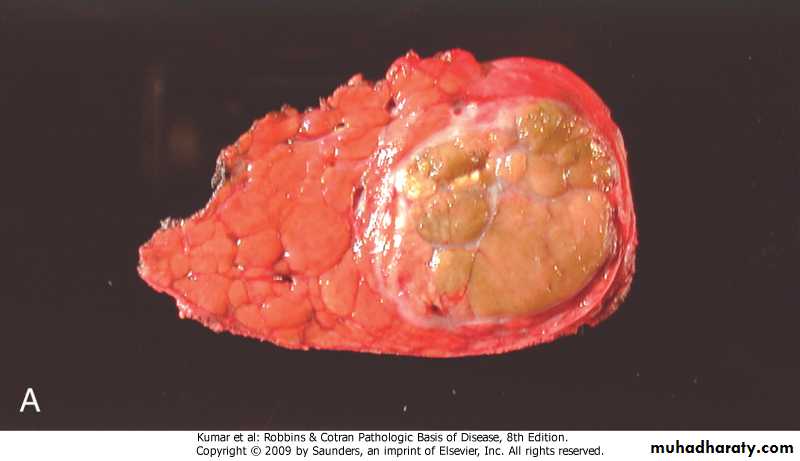

• Morphology -Grossly .well demarcated solitary or multiple nodules up to 30 cm in diameter .yellow-tan & frequently bile-stained . -Microscopy .sheets & cords of hepatocytes .no portal tracts, instead, prominent solitary vessels are present

Liver cell adenoma, yellow-tan, bile-stained nodule